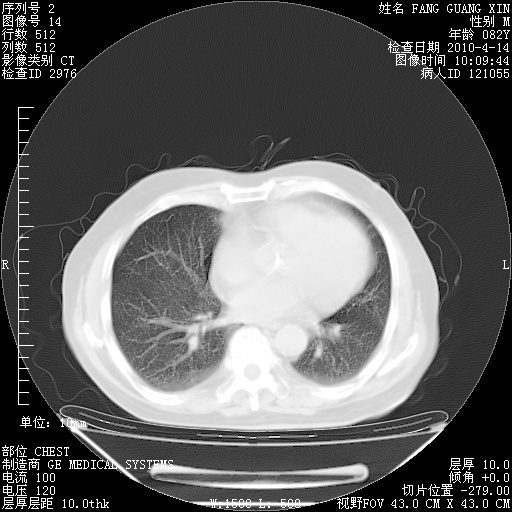

4月14日肺部CT